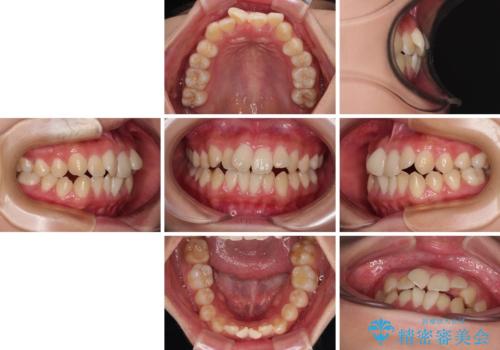

- 前歯のデコボコと唇の閉じにくさを気にして来院された患者様です。

単純に上下左右の第一小臼歯4本を抜歯して口元の突出感を改善することも考えられましたが、上顎骨よりも下顎骨の幅が広いため、より良い咬み合わせを達成することを目的として、急速拡大装置を用いて上顎骨を拡大することとしました。

歯列矯正では基本的に骨格を改善することはできませんが、急速拡大装置(MARPE)を使用することで上顎骨を側方に拡大させることができ、咬合状態を大きく改善することができます。